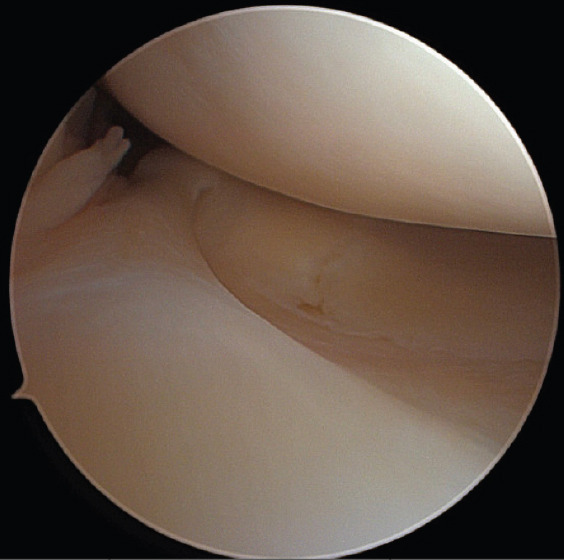

Case report: Our patient is a 38-year-old female who presented to the outpatient orthopedic clinic complaining of right knee pain in the setting of a traumatic kneeling event. She had a past medical history of asthma, polycystic ovary syndrome, and anxiety, but no surgical history related to the knee. She underwent magnetic resonance imaging identified what appeared to be a bucket-handle medial meniscus tear. The patient was brought to the operating room where diagnostic arthroscopy revealed a radial tear at the posterior horn of the medial meniscus as well as an anomalous connection between the anterior and posterior roots. The band specifically ran from the posterior horn of the medial meniscus, then superiorly and along the posterior cruciate ligament, and ultimately attached to the anterior horn of the medial meniscus in an "O" shape. In addition, a large patellofemoral plica was identified overlying the lateral femoral condyle. The tear, plica, and anomalous band were all debrided. The patient was progressing well on her most recent 7-month follow-up visit.